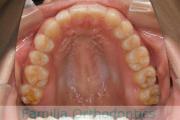

上顎

下顎

前歯の関係など